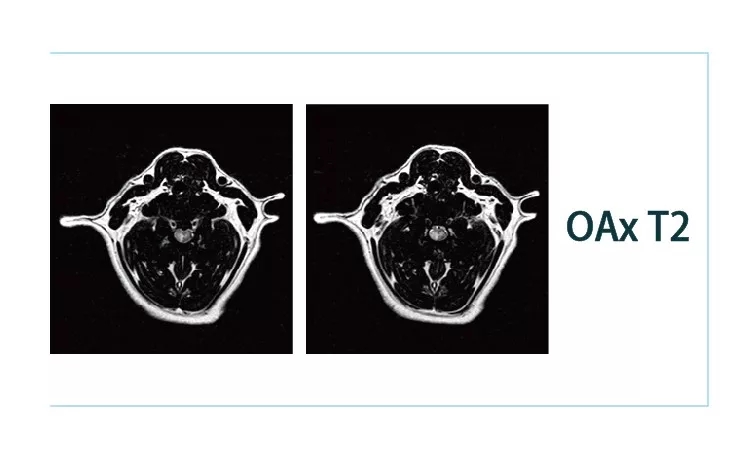

640.webp.jpg640.webp (1).jpg